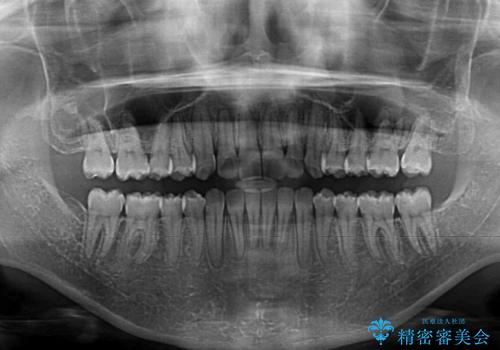

1日22時間の装着時間をしっかり守ってくださったので、予定通り1年で治療を終えることができました。

ディープバイトによる食いしばり癖も解消され、患者様には大変満足していただきました。